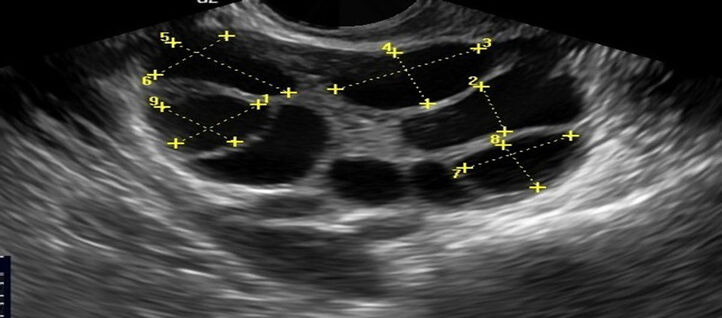

GI RIMON experienced team of fertility specialists provides compassionate, science-based care to diagnose and treat the root causes of female infertility.